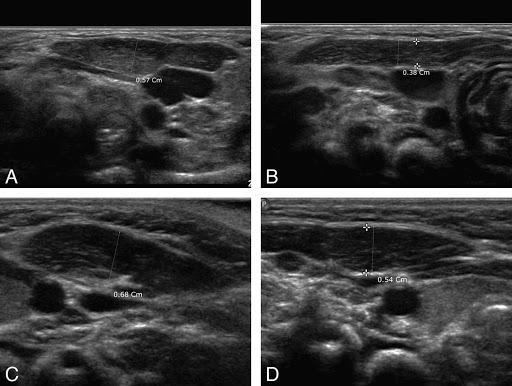

Çocuklarda boyundaki şişliklerin bir diğer sebebi de doğumsal kistik yapılardır. Bu yapılar anne karnında embriyolojik gelişim sırasındaki aksaklıklardan oluşur. En sık gördüğümüz brankial kleft kistleri ve tiroglossal duktus kistleridir. Büyük kistik yapılara yol açabileceği için cerrahi olarak çıkarılması gerekebilir. Brankial kleft kistleri ve tiroglossal duktus kistleri ultrason ile kolaylıkla saptanabilir.